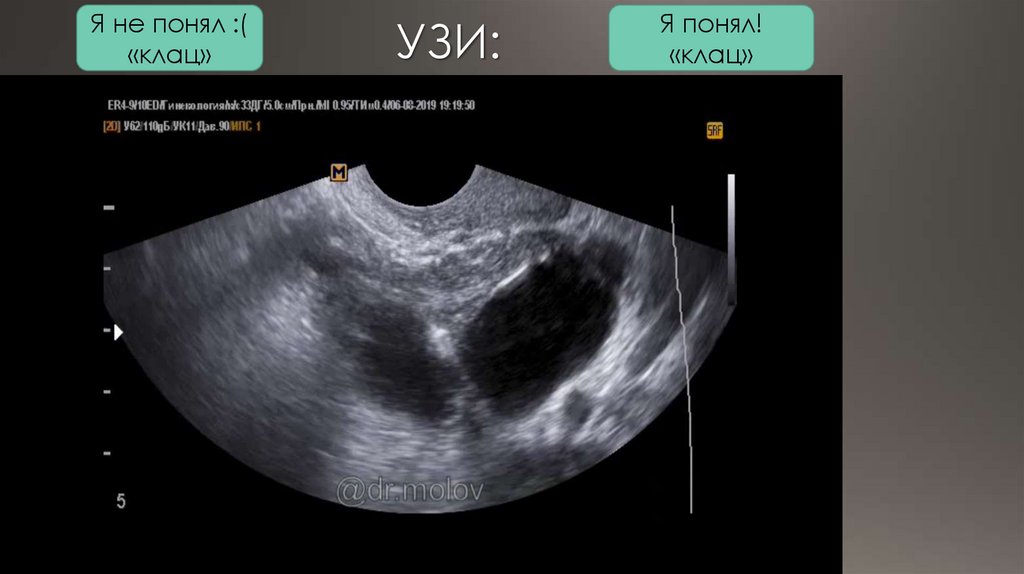

УЗИ:

Я понял!

«клац»